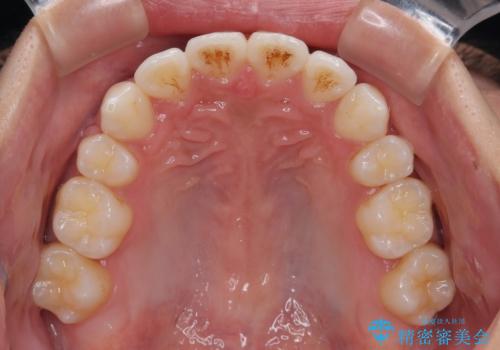

- 八重歯と口元の閉じにくさを気にして来院された患者様です。

非抜歯矯正で歯列を整えると、治療後に口元が今よりも突出する可能性が高かったため、上下左右の第一小臼歯4本を抜歯し、ワイヤー装置にて矯正治療を行うこととしました。

患者様の望んでいた通りの歯列や口元に仕上げることができました。